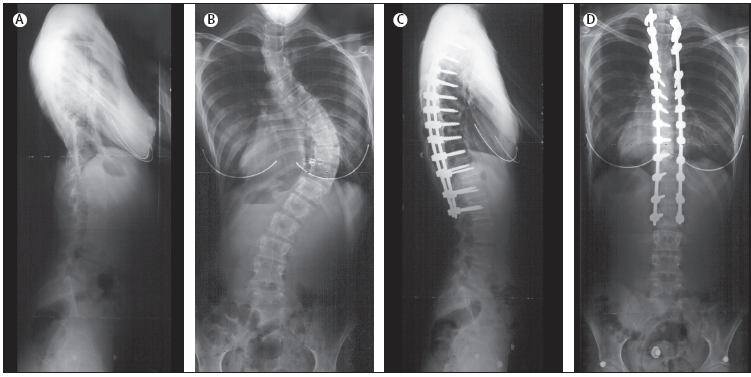

A.

Radiografia laterale preoperatoria; B. Radiografia

posteriore-anteriore preoperatoria; C. Radiografia laterale

postoperatoria; D. Radiografia posteriore-anteriore postoperatoria.

Figura

6. Radiografia di un adolescente con scoliosi toracica idiopatica

trattata chirurgicamente per via anteriore.

A.

Radiografia laterale preoperatoria; B. Radiografia

posteriore-anteriore preoperatoria; C. Radiografia laterale

postoperatoria; D. Radiografia posteriore-anteriore postoperatoria.